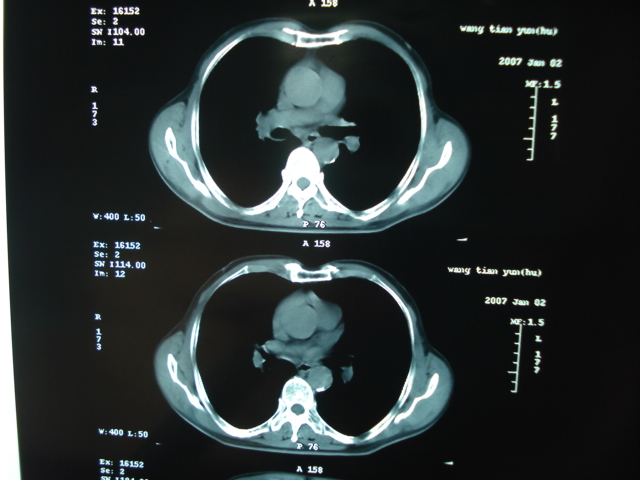

以下是引用狙击手在2007-4-18 20:17:00的发言:[br]原:2007/1/22号ct片:右肺上叶可见片状、云雾状高密度影,右肺上叶后段可见三角形高密度影,尖端指向肺门,右肺上叶后段支气管壁不规则增厚,管腔不规则增厚,纵隔未见肿大淋巴结.[br] 今ct:右肺上叶片状影增大,右肺上叶后段不张及右肺上叶后段支气管壁不规则增厚未见变化,右肺下叶背段支气管壁不规则增厚.[br] 如果考虑肺结核,但从临床证据看竟然没有一项支持肺结核,不知患者是否已经过正规抗结核治疗。没有的话,3个月了前后片看起来变化不大,似乎有不太符合肿瘤征象,不知患者是否抗炎治疗过,下叶支气管增粗还是要高度警惕,同意楼主意见,将常规病理,生化检查再做一遍。[br]

以下是引用狙击手在2007-4-18 20:17:00的发言:[br]原:2007/1/22号ct片:右肺上叶可见片状、云雾状高密度影,右肺上叶后段可见三角形高密度影,尖端指向肺门,右肺上叶后段支气管壁不规则增厚,管腔不规则增厚,纵隔未见肿大淋巴结.[br] 今ct:右肺上叶片状影增大,右肺上叶后段不张及右肺上叶后段支气管壁不规则增厚未见变化,右肺下叶背段支气管壁不规则增厚.[br] 如果考虑肺结核,但从临床证据看竟然没有一项支持肺结核,不知患者是否已经过正规抗结核治疗。没有的话,3个月了前后片看起来变化不大,似乎有不太符合肿瘤征象,不知患者是否抗炎治疗过,下叶支气管增粗还是要高度警惕,同意楼主意见,将常规病理,生化检查在做一遍。[br]